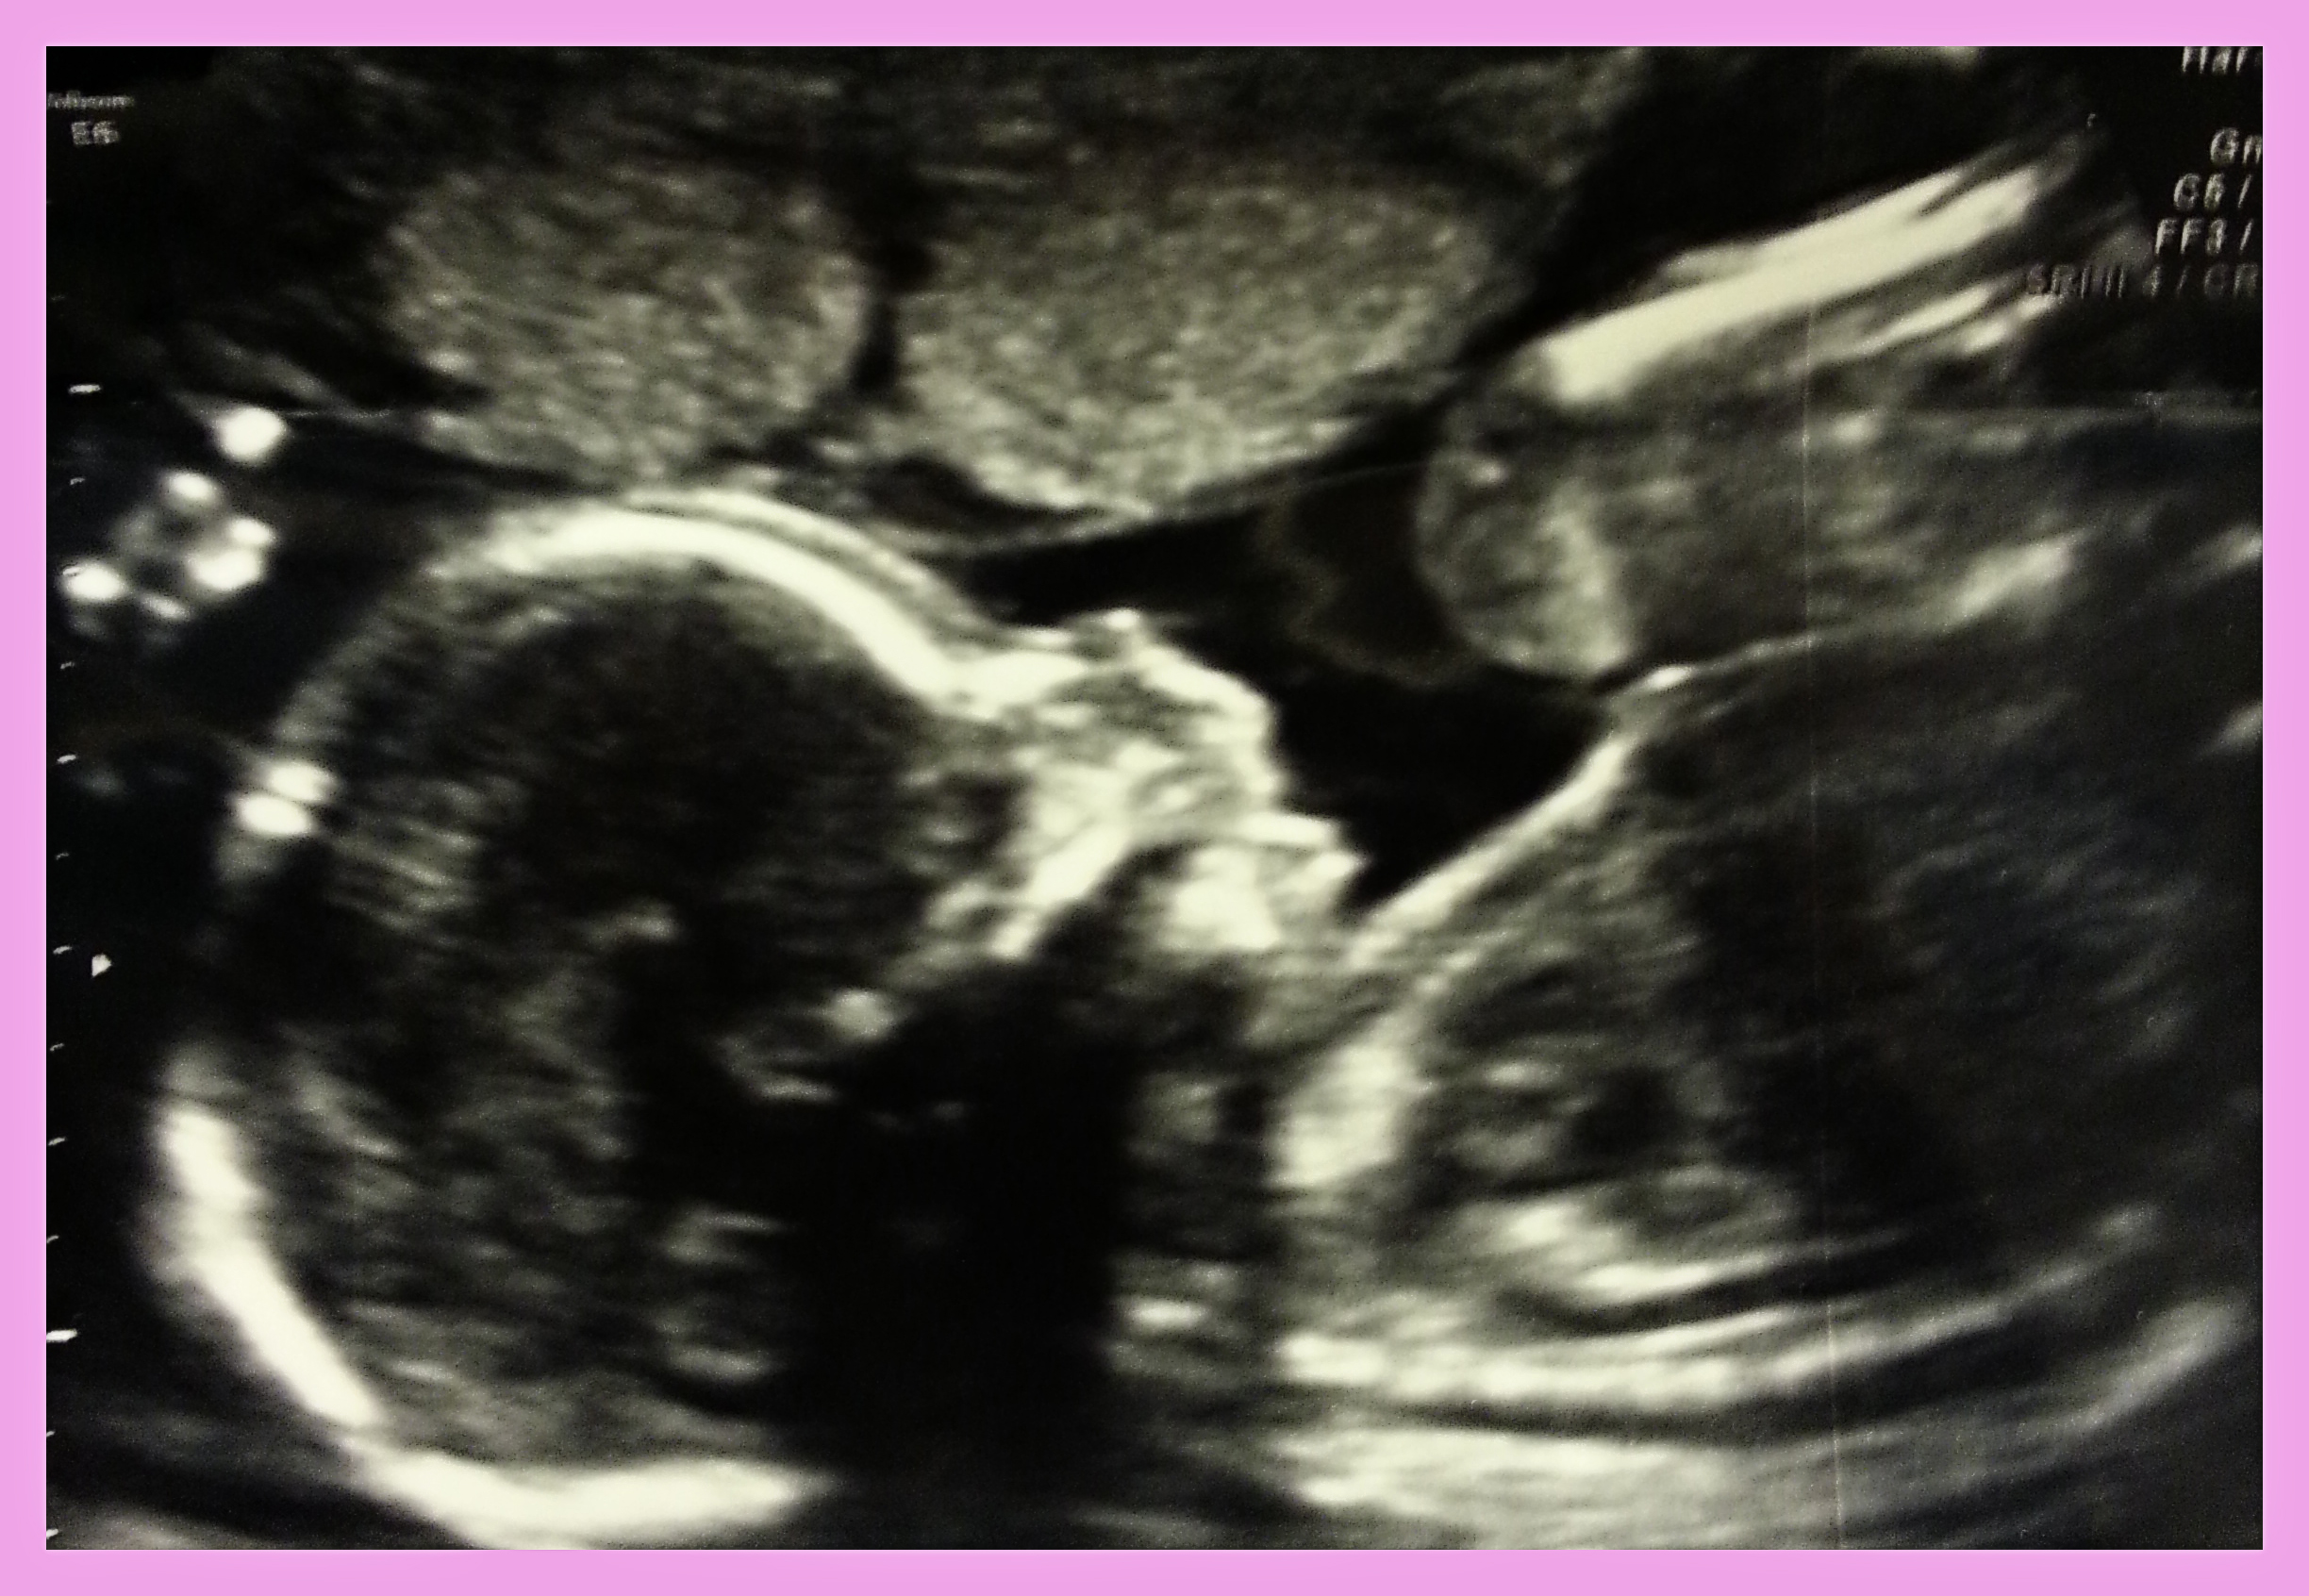

Our little girl got a healthy report from the ultrasound tech!

It was amazing to see how detailed the scan gets with exploring all of the little body parts. She's measuring at about 11 ounces and at the 54th percentile. We did get to see her 3D, but even though mom's a photographer, she wasn't very cooperative for pictures! She had her face buried in the placenta and was completely snuggled up to it! If I can figure out how to put a picture up from my phone, I'll do that. Thanks again for thinking of us today- I feel truly blessed to have such a great support system here!